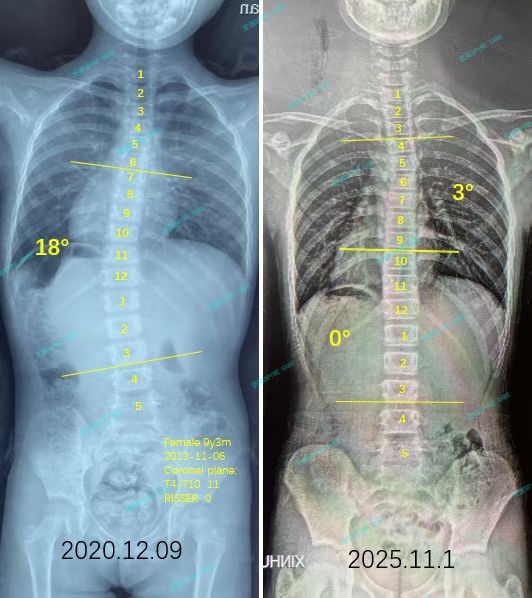

来自家长对衷德的评价(娴娴妈妈)